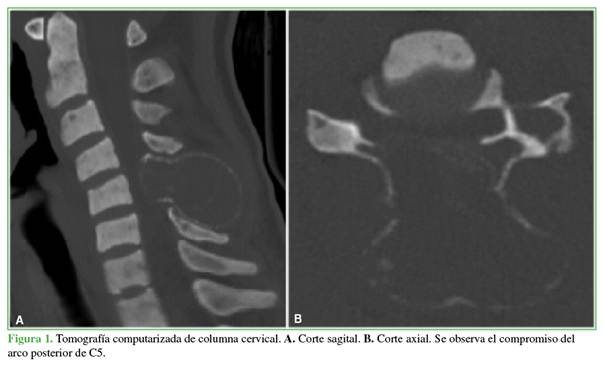

Se solicitaron radiografías y una tomografía computarizada de columna cervical que mostraron una voluminosa lesión osteolítica con márgenes esclerosos en el arco posterior de la 5.a vértebra cervical y extensión a partes blandas adyacentes de dicha región (Figura 1). En la resonancia magnética, se observó una compresión medular severa en la 5.a vértebra cervical (Figura 2).

El tumor pardo, en particular, suele aparecer en la radiografía o el estudio tomográfico como una imagen lítica, multilobulada que puede o no contener márgenes periféricos esclerosos. En la resonancia magnética, se observa una lesión hipointensa en la secuencia T1 e hiper/isointensa en la secuencia T2 con tendencia a la invasión de tejidos adyacentes; cuando se administra un medio de contraste intravenoso suele realzarlo.7,8

En nuestra paciente, el compromiso de la lesión se extendía a todo el arco posterior de C5 y afectaba no solo a las partes blandas paravertebrales, sino también la región epidural posterior generando una compresión medular significativa.